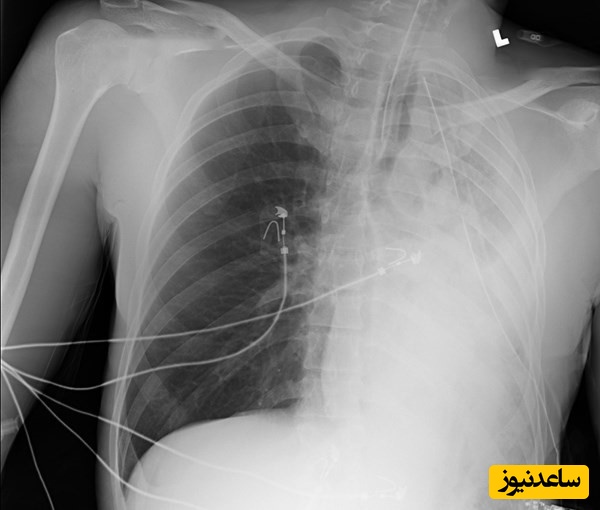

به گزارش سرویس سلامت خانواده پایگاه خبری ساعدنیوز، احساس تنگی نفس شدید، سرفههایی که با خلط کفآلود صورتیرنگ همراه است و تنفس صدادار (ویزینگ) میتواند از علائم هشداردهنده آب آوردن ریه یا ادم ریوی باشد. این وضعیت اورژانسی زمانی رخ میدهد که مایعات از عروق خونی کوچک ریه به داخل آلوئولها (کیسههای هوایی) نشت میکنند. این تجمع مایع، تبادل اکسیژن و دیاکسید کربن را مختل کرده و به سرعت منجر به مشکلات تنفسی جدی میشود. درک دلایل بروز این عارضه و آشنایی با روشهای درمانی آن، گامی مهم در جهت مدیریت و پیشگیری از آن است.

درمان آب آوردن ریه یک اورژانس پزشکی است و هدف اصلی آن بهبود تبادل اکسیژن و درمان علت زمینهای است.

اکسیژندرمانی: اولین قدم، رساندن اکسیژن کافی به بدن است. این کار از طریق ماسک صورت، کانولای بینی یا در موارد شدیدتر، با استفاده از دستگاه تنفس مصنوعی (ونتیلاتور) انجام میشود.